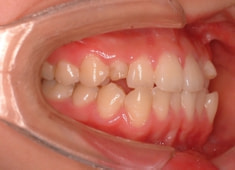

症例紹介

先天欠如歯両側上顎3番

治療法:フルパッシブブラケット:T21

治療前